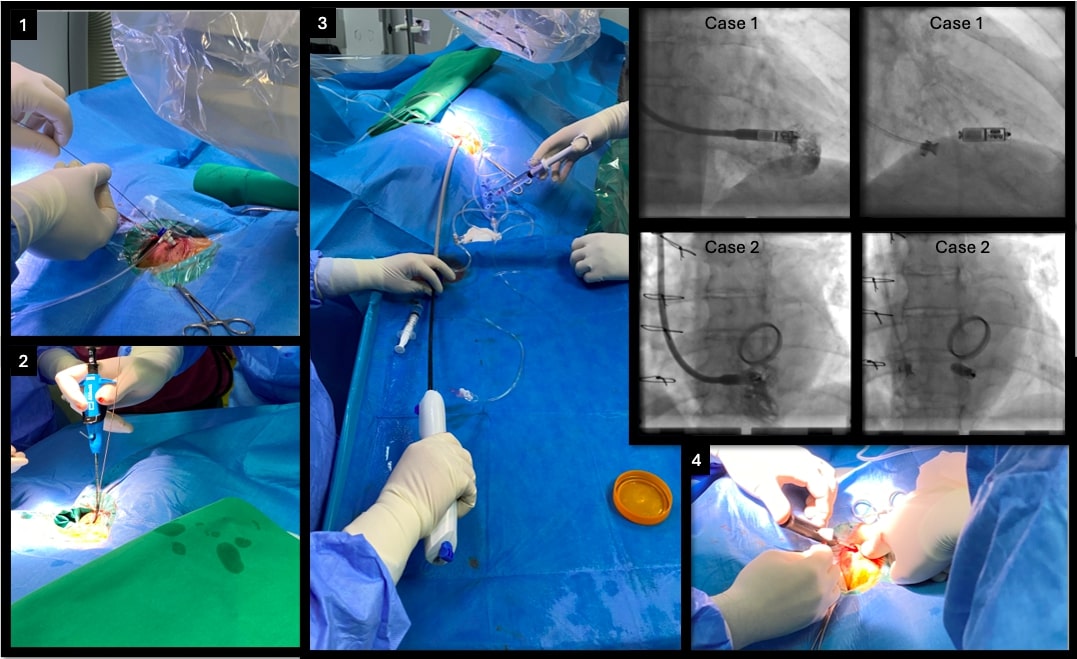

In both cases, the RIJ approach was deemed the only safe and feasible option. Procedures were performed under local anesthesia in the electrophysiology lab and were identical for both patients. Each was placed in the standard supine position with the C-arm rotated 90° leftward to allow right-neck access and facilitate manipulation of the Micra delivery system. Initial ultrasound confirmed a patent RIJ with a diameter greater than 1 cm. Ultrasound-guided puncture was performed, and a 6F sheath was inserted to secure access (Figure; panel 1). After placement of a 0.035-inch stiff guidewire, the sheath was removed, and 2 Perclose ProGlide sutures (Abbott) were deployed at 90° angles using the double preclose technique (Figure; panel 2). A 9F sheath was then inserted for superior vena cava venography, which confirmed unobstructed flow to the right atrium. Serial dilatation (14F to 18F) was performed, allowing safe advancement of the 27F Micra introducer sheath (Figure; panel 3). To minimize tip force, the Micra delivery system was advanced in a flexed configuration across the tricuspid valve. Under biplane fluoroscopy (RAO/LAO 45°), mid-septal positioning was confirmed (Figure; superimposed panels). Device deployment followed satisfactory electrical measurements. Fixation was confirmed by a pull-and-hold test, with at least 2 of 4 tines engaged. The tether was then cut, and the delivery system along with the sheath was withdrawn. Hemostasis was achieved using the pre-placed sutures (Figure; panel 4). The fluoroscopy times were 9.06 and 5.05 minutes with low radiation doses (air kerma: 134 mGy and 100 mGy) for each case, respectively. Both patients were mobilized immediately. No puncture site-related complications were seen.